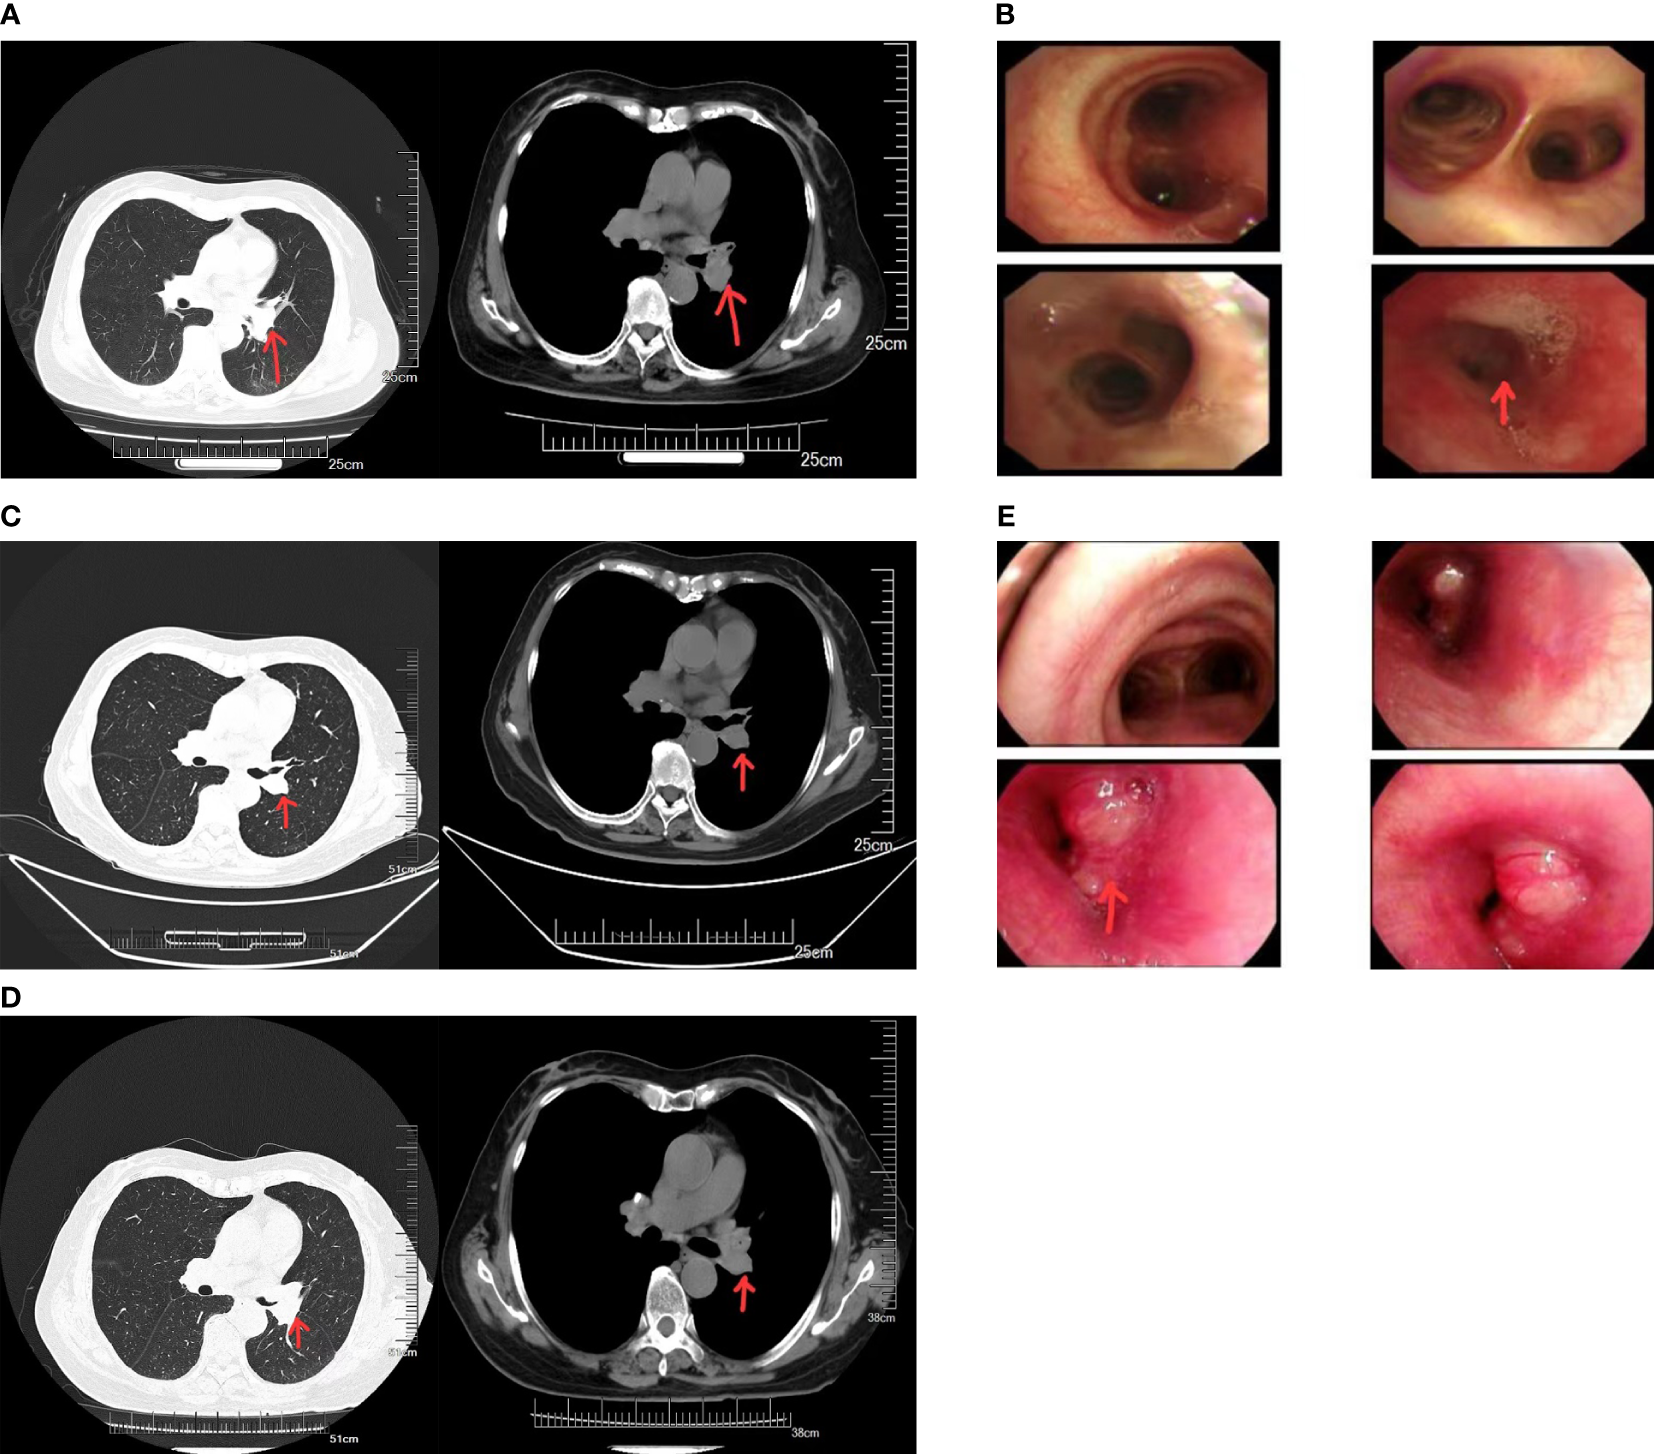

The patient was a 67-year-old woman. Seven months ago, she exhibited no obvious reasons for cough or white sputum. At times, she coughed up blood. She did not receive systematic diagnosis and treatment. One month later, she felt suffocation in the anterior chest area with poor breathing; again, she did not pay attention to these signs. Only after the gradual worsening of the symptoms did she visit our hospital. Chest computed tomography (CT, Figure 1A) revealed the presence of a soft tissue mass in the left hilum of her lung. The lesion was 32 × 25 mm in size, with uneven density and a CT value of 32 HU. It was protruding into the bronchus of the upper lobe of the left lung. There was bronchial wall thickening, distal lumen obstruction, and many mediastinal lymph nodes. Bronchoscopy (Figure 1B) revealed mucosal swelling at the opening of the left upper lobe, superficial irregular hyperplasia, lumen occlusion, lesions involving the upper and lower interlobar ridges, and lumen stenosis at the opening of the left lower lobe. Pathological examination of the opening of the left upper lobe revealed a tumor morphology consistent with squamous cell carcinoma (non-keratinizing type). The patient had a smoking history of 20 years and a smoking index of 400 years. A physical examination found no obvious abnormality. Tumor marker (sample number 20230324HYA001) analysis showed the following: abnormal prothrombin, 39.740 mAU/ml (reference value: 11.12–32.01 mAU/ml); cytokeratin 19 fragment at 2.42 ng/ml (reference value: 0–2.08 ng/ml); and premenopausal ROMA value of 12.00% (reference value: 0%–7.4%); the other markers were normal. Head-enhanced magnetic resonance imaging, abdominal CT, whole-body bone scan, and other auxiliary examinations suggested no metastasis or surgical contraindications. The tumor stage was T2aNxM0, and the clinical stage was IB as per the guidelines for primary lung cancer diagnosis and treatment of the China Health Commission (2022 edition). As a result, surgery was indicated. The preoperative pulmonary function test suggested mild obstructive ventilatory dysfunction. However, after being informed of the surgical risks, the patient and her family declined surgery. As a substitute, preoperative chemotherapy combined with neoadjuvant immunotherapy sintilimab and gemcitabine–platinum-containing drug for squamous cell carcinoma was prescribed as per the first-line drug treatment guidelines for primary lung cancer diagnosis and treatment (2022 edition). Prior to chemotherapy, the patient scored 50 on the Karnofsky Performance Scale (KPS), which precluded chemotherapy, and only immunotherapy was administered. Due to economic issues, the PD-1 test was not performed. In the end, sintilimab immunotherapy was carried out for 21 days as one cycle. The lung cancer guidelines do not specify the number of immunotherapy cycles. The patient’s symptoms significantly improved after three cycles. Chest CT (Figure 1C) showed that the tumor size was reduced to 21 × 24 mm. From the good result of neoadjuvant immunotherapy, surgery was recommended again. Yet, the patient and her family refused it again due in part to the good effects of immunotherapy, plus cost consideration and other related reasons. Therefore, maintenance treatment was administered as per the primary lung cancer diagnosis and treatment guidelines, which can be selected for patients who attain disease control after first-line treatment. If no disease progression and tolerable adverse reactions are obtained from using these immune checkpoint inhibitors, these treatment cycles can be administered for 2 years. However, after the fourth cycle of sintilimab, the symptoms began to worsen. Before the fifth cycle, chest CT (Figure 1D) revealed that the tumor size had increased to 31 × 24 mm. Bronchoscopy (Figure 1E) revealed that the lumen was blocked by new growth in the lower portion of the left main bronchus, with an irregular layer of cell proliferation. The lower portion of the left main bronchus was biopsied. Pathology revealed bronchial carcinoma. Immunohistochemical staining combined with morphology supported the diagnosis of small cell carcinoma. At this time, the patient scored 60 on KPS. Considering that the patient could likely tolerate the side effects of chemotherapy, etoposide plus nedaplatin was recommended. After chemotherapy, chest high-resolution CT revealed a reduced lesion size of 20 × 18 mm, suggesting that the tumor had responded to the new treatment regimen.

Figure 1 (A) Computed tomography (CT) images of the patient before neoadjuvant therapy. (B) Results of the first bronchoscopy. (C) CT images of the patient after three cycles of sintilimab immunotherapy. (D) CT images of the patient after five cycles of sintilimab immunotherapy. (E) Results of the second bronchoscopy.